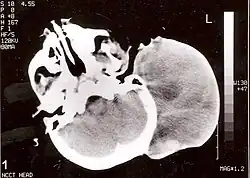

| Non-contrast CT scan of head showing a large mass without any intracranial extension. The diagnosis was post-auricular congenital alveolar rhabdomyosarcoma. | |